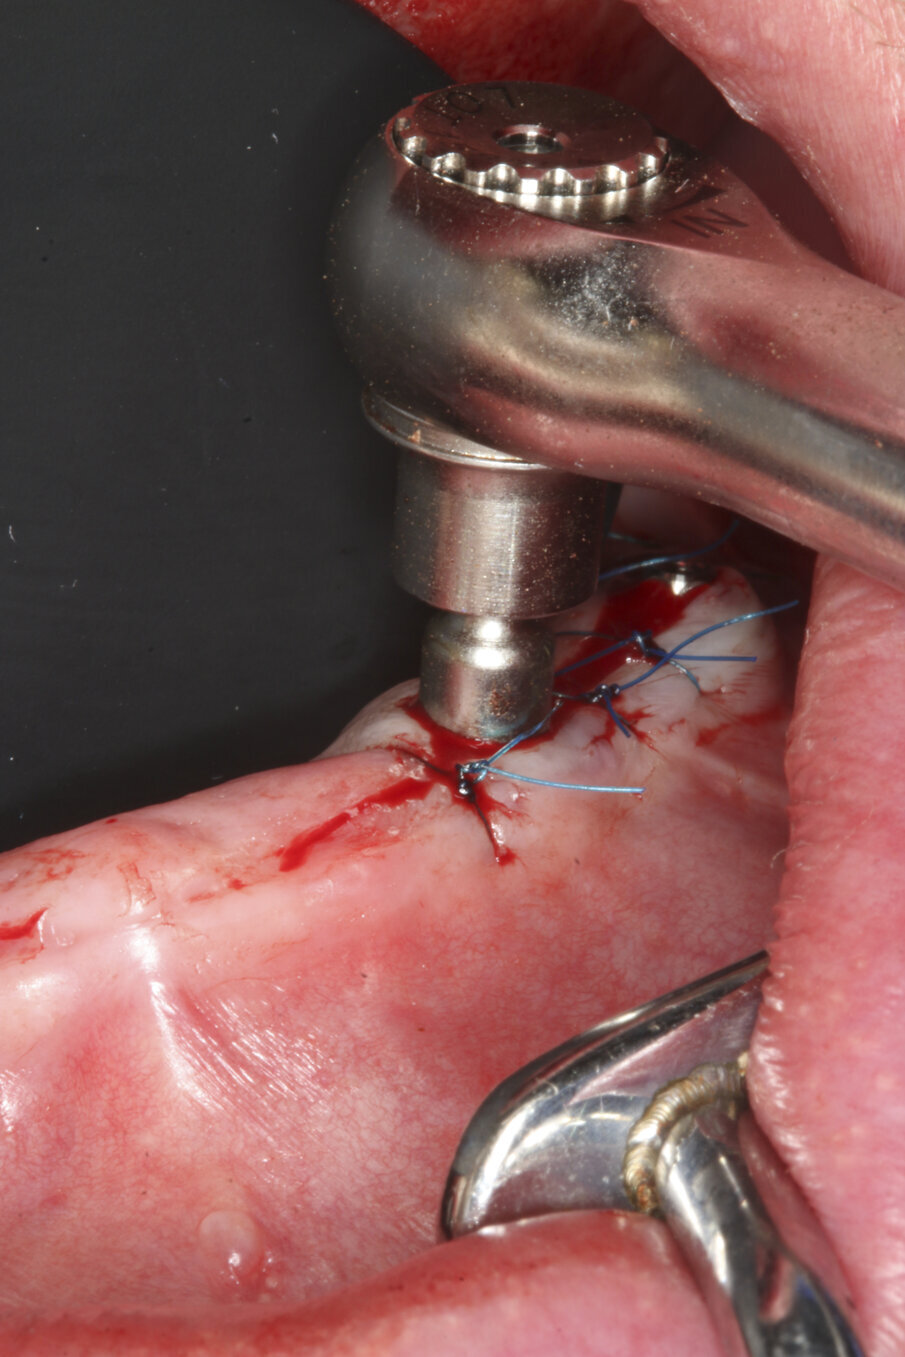

Prior to surgery, intra-oral scans of the edentulous upper jaw and dentate lower jaw were performed. The existing denture was used first as a surgical guide and then as a provisional prosthesis, after removing the palate (Fig. 4). Immediately after implant placement (Figs. 5–10), abutment position was registered with an intra-oral scan (Fig. 11). The provisional prosthesis was prepared fromthe existing denture (Figs. 12 & 13) and then the Atlantis BridgeBase was designed (Fig. 14).

Fig. 8: The abutments were torqued to 25 Ncm.